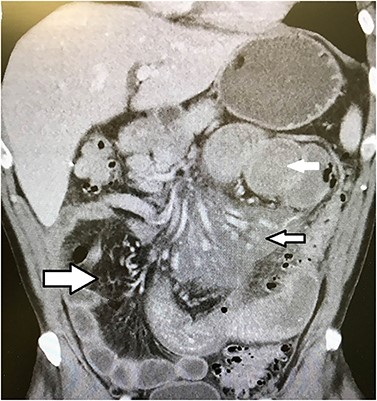

CT scan of the abdomen showing dilated proximal small bowel (solid white arrow), inflammatory changes in the proximal small bowel mesentery around the superior mesenteric artery (small black and white arrow) and normal distal mesenteric fat (large black and white arrow).

On physical examination, he was mildly tachycardic, diaphoretic, normotensive and had a mildly distended abdomen with diffuse tenderness without peritoneal signs. Laboratory results showed a mild leukocytosis with a white blood cell count of 14 K and hypochloraemia, hyponatraemia and hypokalaemia. After intravenous fluid resuscitation, computed tomography of the abdomen showed very dilated proximal small bowel and stomach with extensive inflammatory changes and fat stranding throughout the proximal mesentery (Fig. 1). The distal and colonic mesentery appeared normal.